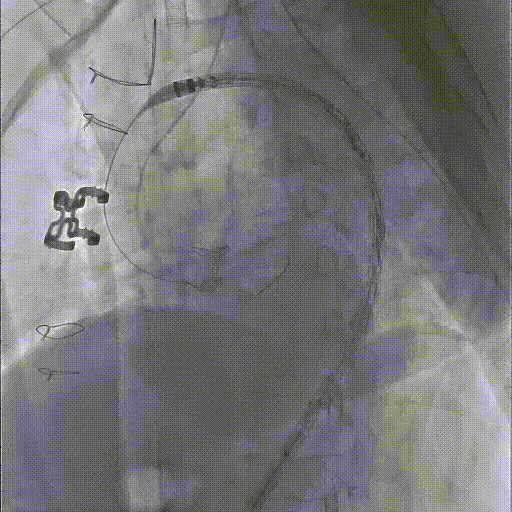

★ Case 1

男性,42岁,胸痛3天;

既往史:高血压,规律服用降压药物;

手术史:10年前外院行主动脉腔内修复+左颈总及左锁骨下烟囱支架植入;

夹层动脉瘤CTA:逆撕A型主动脉夹层,升主动脉及无名动脉见夹层累及,左颈总及左锁骨下动脉烟囱支架。

剪除部分覆膜支架及左锁骨下烟囱支架

植入术中单分支支架

术中单分支支架开窗及加固